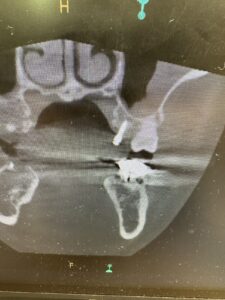

インプラントアンカーを入れている所

実際に入った所

入った後にCTで確認中

📸 写真でもわかるように、

ミスのないよう真剣な表情で取り組んでいます💡